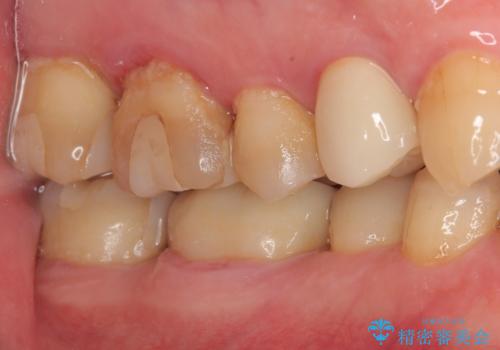

- 食事中に歯が欠けてしまった事を主訴に来院された患者様です。

小臼歯が広範囲に欠けてしまっています。

部分的な詰め物では再びかけてしまうリスクが高いため、オールセラミッククランにて補綴治療をすることとしました。

精度の高い被せものは二次う蝕のリスクが低いです。